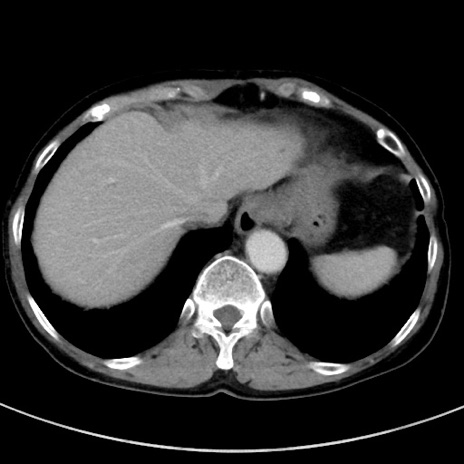

症例23(横断像)

【症例】70歳代女性

【主訴】下腹部痛・嘔吐

【現病歴】2日前より腹痛あり。昨日嘔吐あり。症状改善しないため来院。

【既往歴】胃GISTに対して胃部分切除後。

【身体所見】BT 37.1℃、BP 128/77mmHg、腹部:平坦・軟、下腹部に圧痛あり。

【データ】WBC 10200、CRP 0.31